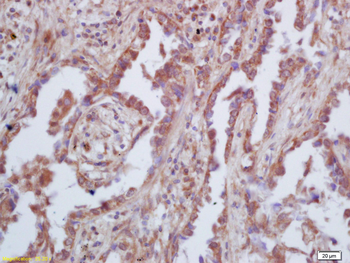

GAS 6 Rabbit Polyclonal Antibody

IF, IHC-Fr, IHC-P, WB

应用稀释比例:WB=1:500-2000, IHC-P=1:100-500, IHC-F=1:100-500, IF=1:100-500